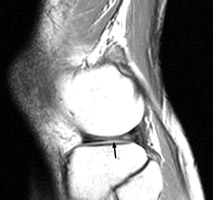

Diagnosis:Bucket-handle tear of the menisci Discussion:Multiple sagittal T1 weighted images which reveal loss of the normal bow-tie appearance of the meniscus. The "absent bow tie sign" is another good sign of a bucket handle tear of the meniscus. The absence of the normal bow-tie is secondary to the displaced fragment which makes up the "handle" of the bucket. Requirement for the absent bow tie sign mandates that the normal requirement of at least two adjacent sagittal images with a normal meniscal body segment appearance is not present. References: